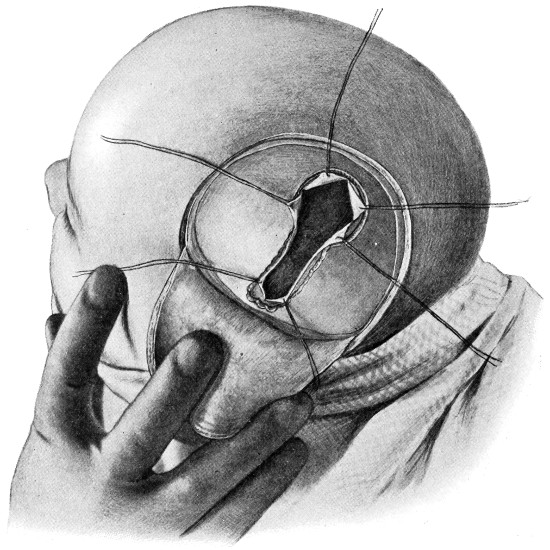

| 9 and 10. The technique of trephining | 22 |

Craniotomy, or osteoplastic resection of the skull, was first carried out by Wagner. It is proposed to describe that method only which, by experience, has been found to meet all requirements—the formation of the osteoplastic flap by means of the hand-trephine, Gigli’s saw, and de Vilbiss’s forceps.

The protective gauze dressing and scalp-tourniquet are applied

as before. A large ![]() -shaped

incision is made in such a manner as

to include the area which it is desired to expose. The two vertical

limbs of the incision should converge to such a degree as to allow of

the subsequent ready fracture of the flap along its base. The knife

is entered at one extremity, carried down to the bone, and the three

incisions rapidly made, one after the other. Along the line of each

of the three incisions, the pericranium is stripped away from the bone

so as to allow of adequate exposure. At the anterior and posterior

angles of the flap the tissues are retracted a little more, permitting

the application of a half-inch diameter trephine. Here the two

trephine-holes are bored—with the usual precautions against damage

to the dura mater—and the two disks of bone elevated and removed.

Between these two trephine-holes the dura mater is separated from the bone and the special director introduced, entering at the one hole, emerging at the other, and lying throughout between the dura and the bone. The saw is now passed along the groove of the director, the handles affixed, and the bone intervening between the two trephine-holes divided, not straight out to the surface, but bevelled or cut in such an oblique manner that the bone-flap, when replaced, rests on a ledge (see Figs. 17-19). The sawing process[26] generates considerable heat, and the assistant should be instructed to keep up irrigation with saline solution or sterilized water. The sawing is carried out by steady side-to-side traction, without jerks; if the saw breaks, the special handle may be attached, thus obviating the necessity of introducing a new saw.

Fig. 17. First Stage in the Formation of an Osteoplastic Flap. Gigli’s saw, protected from the dura mater by the special director, passing between the two trephine-holes. For further description, see text.